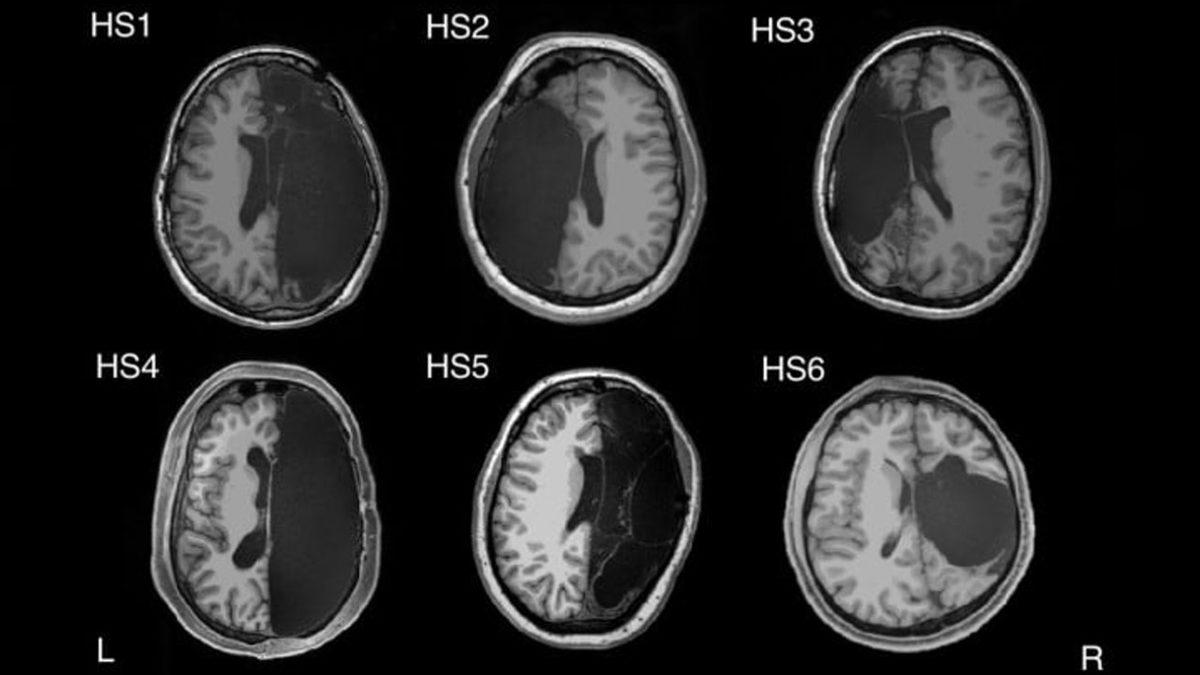

Çocukluğundan beri epilepsiyle savaşmış ve ilaçlarla tedavide başarılı olunamamış 4’ü erkek 2’si kadın olmak üzere 6 hasta, bu bilimsel araştırma için mercek altına alındı. Ameliyatla beyinlerinin yarısı çıkarılan hastaların yoğun epilepsi nöbetlerinden kurtulması hedefleniyordu.

Kaliforniya Teknoloji Enstitüsü’ndeki çalışmada, beyninin yarısı olmayan bu 6 kişinin MRI (manyetik rezonans görüntüleme) sonuçları incelenerek, sağlıklı insanların MRI sonuçlarıyla karşılaştırıldı.

Yapılan incelemenin sonucu herkesi şaşırttı! Radyolojik görüntüler referans alındığında; yarım beyinle yaşamlarına devam eden bu 6 insanın beyin aktiviteleri ile sağlıklı insanların beyin fonksiyonları arasında büyük ölçüde benzerlik olduğu görüldü.